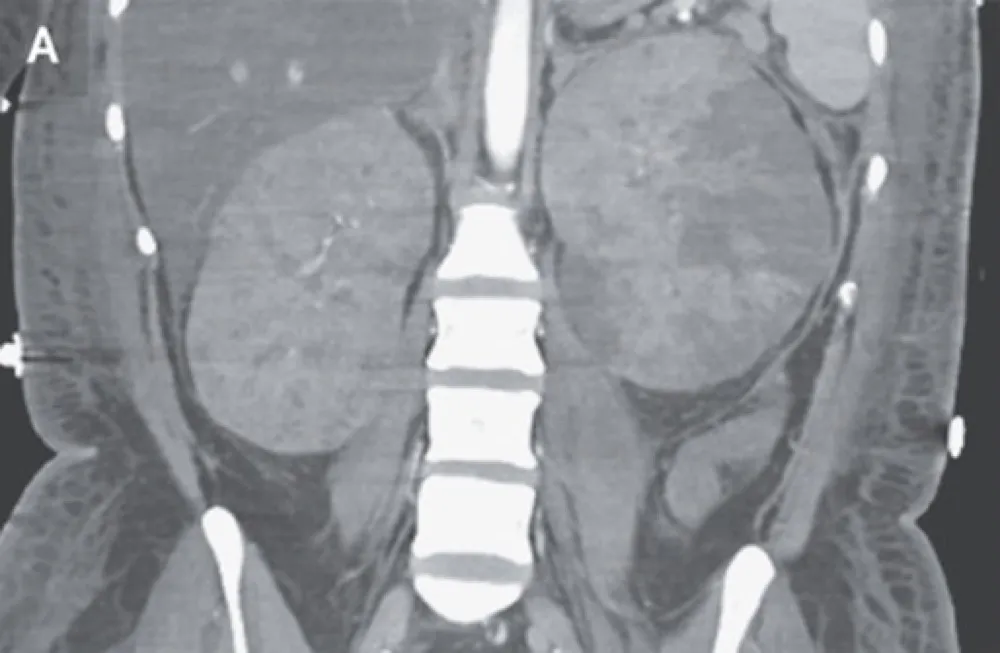

DRC indeterminada ou você esqueceu de fazer o básico? Veja tudo aqui

DRC indeterminada ou você esqueceu de fazer o básico? Veja tudo aqui

DRC “indeterminada” raramente é falta de diagnóstico — quase sempre é falta de método. Tempo de evolução, urina bem avaliada, USG renal e história clínica dirigida mudam conduta e evitam erros comuns na prática nefrológica.